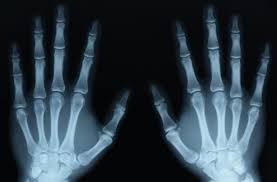

Tính truyền thẳng và đâm xuyên: Tia X truyền thẳng và có khả năng xuyên qua vật chất, qua cơ thể người. Sự đâm xuyên này càng dễ dàng khi cường độ tia càng tăng. Chính vì độ xuyên sâu của tia X cao nên người ta dùng để chụp những bộ phận cứng như: xương, răng, không dùng để chụp mô

Chụp X quang không chuẩn bị bao gồm các kỹ thuật chụp X quang các bộ phận của cơ thể như chụp xương khớp, chụp bụng, chụp sọ não, chụp cột sống, chụp phổi, chụp hệ tiết niệu.v.v. không sử dụng được chất cản quang.